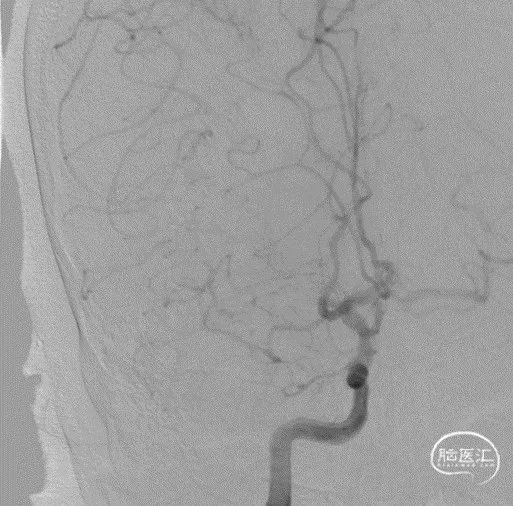

脑血管造影:右侧大脑中动脉M1段闭塞,代偿不足。

选取工作角度造影,测量病变长度。

微导丝辅助微导管通过闭塞段,以赛诺神畅Neuro LPS-1.5-15mm球囊分次扩张闭塞段。

球扩后造影见闭塞段恢复正向血流M1段远端夹层表现。